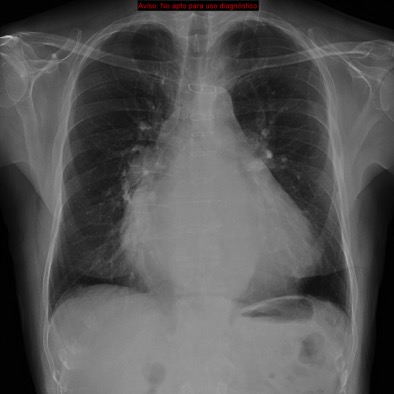

Solución: Es un estudio Normal. Silueta cardiomediastínica y parénquimas pulmonares sin alteraciones significativas.

CASO: sospecha de neumonía.

Hallazgos:

- En un principio podríamos decir que existe un aumento de densidad retrocardiaco que podría ser compatible con condensación neumónica a dicho nivel, sin embargo estamos ante una placa poco inspirada, lo cual puede llevarnos a cometer errores diagnósticos.

- Se recomendó volver a realizar la radiografía, observar a continuación:

Ya no se observa el aumento de densidad retrocardiaco, la placa es normal.

INSPIRACIÓN: Una placa bien inspirada es aquella en la que se observar 6-7 arcos costales anteriores o 10-11 arcos costales posteriores. Lo contrario puede producir imágenes falsas de condensaciones o de seudocardiomegalia.